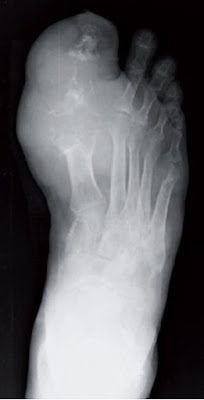

Figura 1. Afectación de 1° MTF en gota. Aumento de partes blandas que se corresponde con depósitos de UMS (tofos). No hay cambios significativos a nivel de la mineralización.

- Aumento de partes blandas en fases aguda secundarias a la inflamación periarticular y en las crónicas a depósitos de urato monosódico (UMS) o tofos. A nivel radiográfico los tofos se encuentran típicamente como nódulos excéntricos y yuxtaarticulares de tejido blando. En su proximidad se observan comúnmente erosiones óseas con márgenes escleróticos y bordes sobresalientes. Figuras 1, 2 y 4

- Ausencia de alteración de la mineralización (no osteopenia yuxtaarticular). Figuras 1 y 2